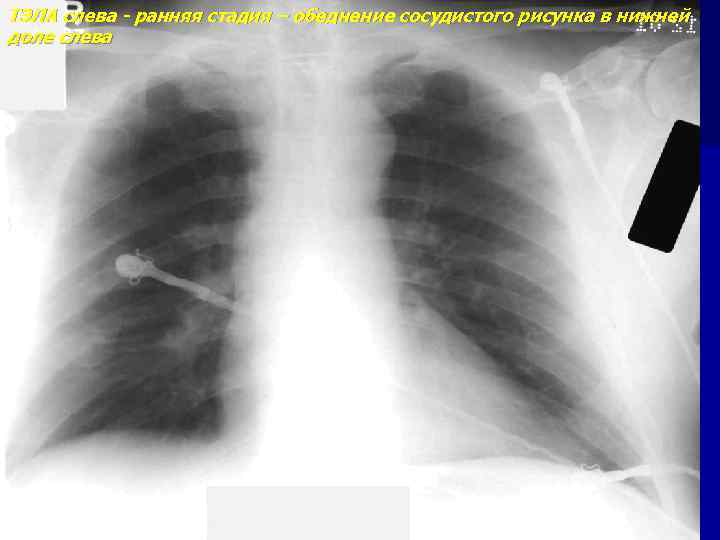

ТЭЛА слева - ранняя стадия – обеднение сосудистого рисунка в нижней доле слева